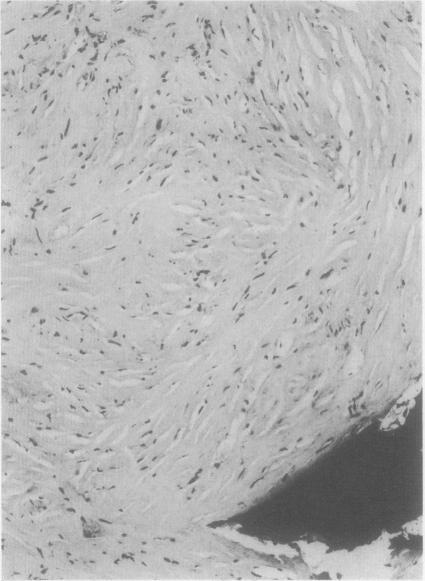

Bony metastases in desmoplastic pleural mesothelioma.

Thorax. 1988 Feb;43(2):155-6. doi: 10.1136/thx.43.2.155.

PMID:3353889

https://cdn.ncbi.nlm.nih.gov/pmc/blobs/b41c/1020760/5810e58d7e4f/thorax00266-0076-a.jpg

https://cdn.ncbi.nlm.nih.gov/pmc/blobs/b41c/1020760/f38533de5172/thorax00266-0075-a.jpg